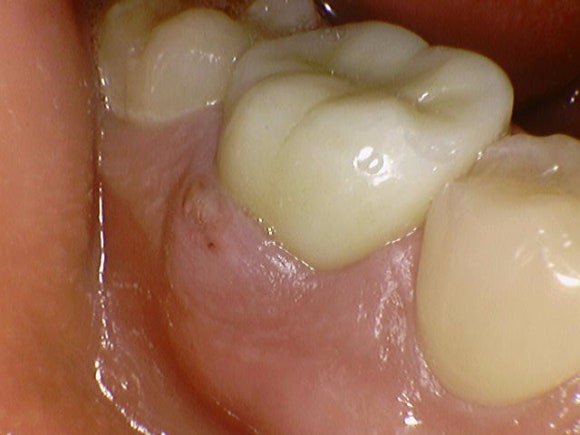

올 초 저에게 오신 30대 남성분입니다.

전반적으로 치아 관리 상태가 매우 우수합니다.

오른쪽 아래 치아에

불과 6개월 전에 신경치료를 받으셨다고 합니다.

그간 아프진 않았지만,

어느 날 잇몸으로 고름주머니가 불거진 것을 확인하셨다고 합니다.